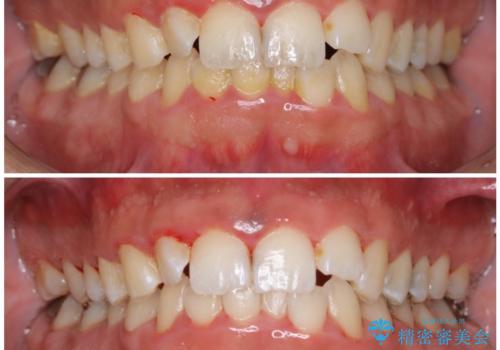

- 結婚式を控えているため、クリーニング希望とのことで来院されました。歯科医院がかなり久しぶりとのことでした。

全体の染め出しを行い、歯科衛生士による専門的自費クリーニング(PMTC)60分コースを行いました。

クリーニングを行うことで、汚れがを取り除くだけではなく、口臭予防にもなります。

また、ご自身本来の歯の色になり自然な明るさになります。